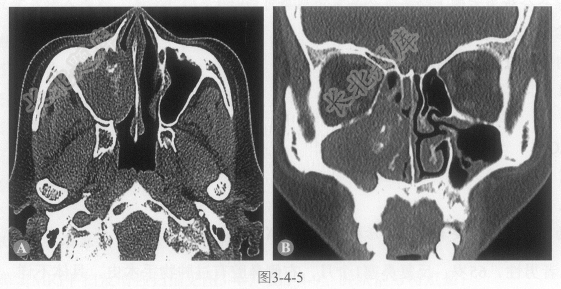

- 单项选择题1.下列征象描述,哪项不正确:

A、右侧中鼻道及右侧上颌窦内见一软组织密度肿块充填,大小约38mm×40mm

B、肿块内见斑点状高密度影

C、右侧上颌窦内侧壁骨质吸收,右侧下鼻甲轻度受压

D、右侧额窦、筛窦黏膜增厚

E、右侧上颌窦各骨壁溶骨性骨质破坏

- 单项选择题2.右侧上颌窦内的高密度影可能的病理基础,下列哪项不正确:

- 单项选择题3.可能的诊断: